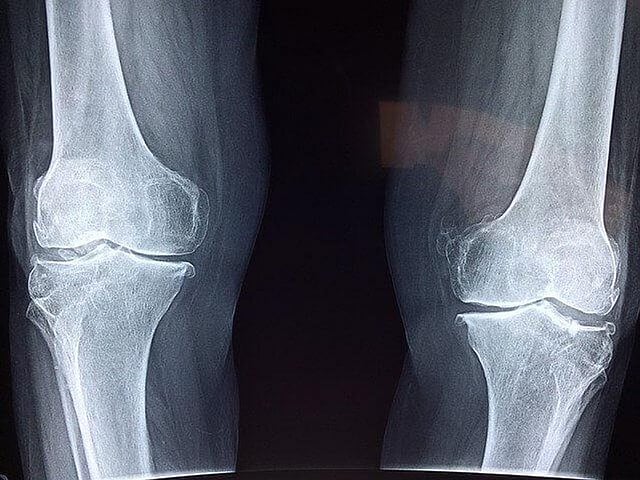

Twelve months after surgery, participants in the exercise group had higher bone mineral density measurements at the lumbar spine and the forearm compared with those in the control group.

Also, participants who attended at least half of the exercise sessions had higher bone mineral density at the femoral neck than those in the control group. The findings suggest that an exercise program is an effective strategy to ameliorate bone health in post-bariatric surgery patients.